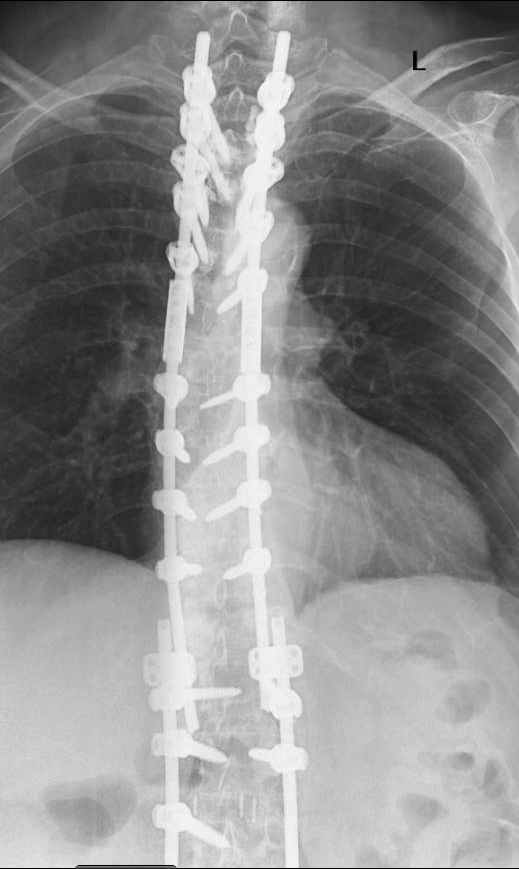

Screen Shot 2021-04-23 at 4.56.45 PM (1).PNG